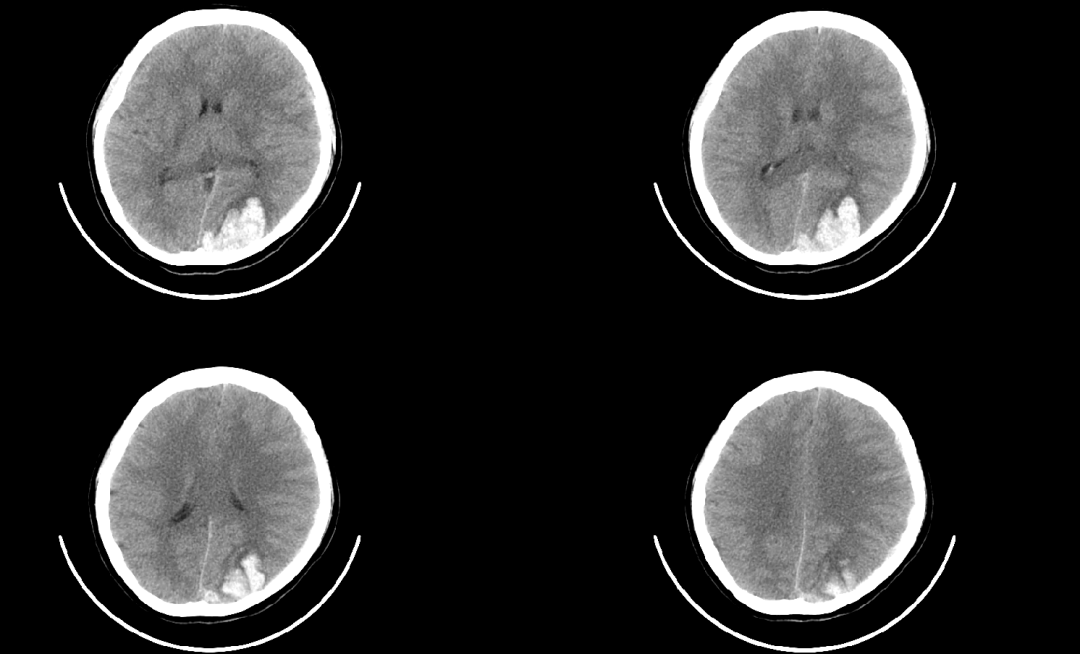

病例2

患者因“突發(fā)視物模糊并頭痛2小時”入院?;颊呤人?,精神差。CT提示:“左枕葉腦出血、腦血管畸形”,病情危重,神經(jīng)外科團隊完善檢查,為患者進行腦血管介入微創(chuàng)手術治療,最終順利康復出院。